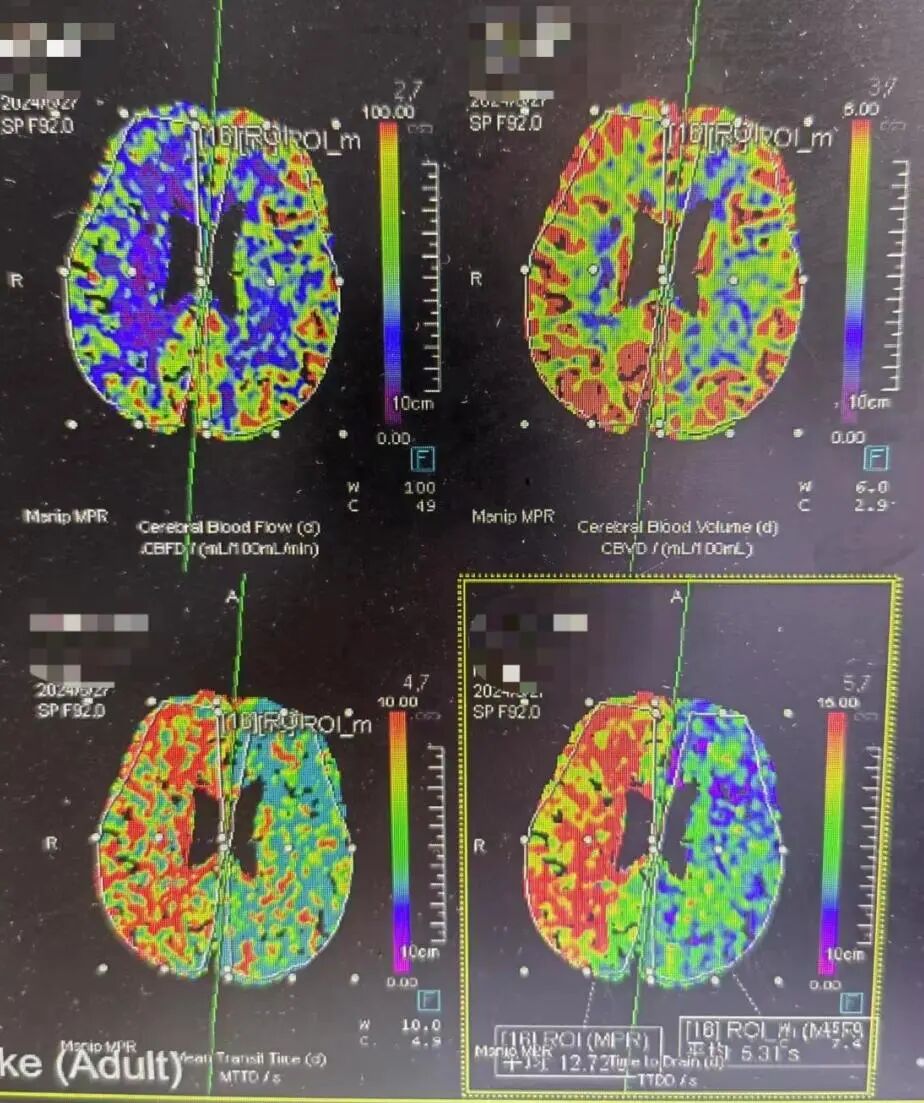

6月27日

CTP

强化药物治疗后,症状逐渐加重,CTP示右侧半球大面积低灌注区。